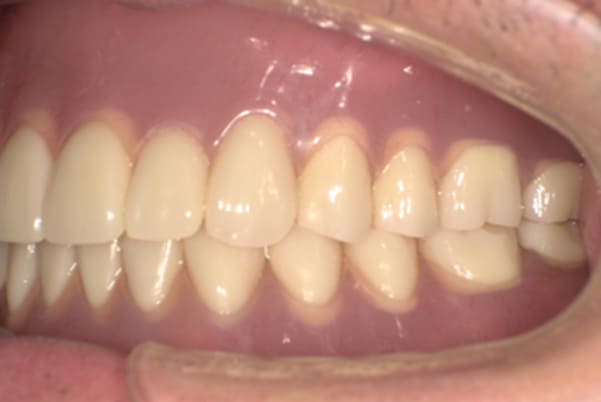

ご自身の歯に負担の少ないバネ、また見た目も改善

ご自身の歯に負担の少ないバネ

銀歯からセラミック歯に

バネをかける歯は繋げることで強度を増し、歯への負担を軽減し、歯の寿命を長くする設計へ。

バネがかかる歯の被せ物は、歯への負担を減らし、入れ歯が動きにくいようになる形態をあらかじめ付与することで、より入れ歯の機能が高まります。

治療を行う際、被せ物や入れ歯は、別々に考えるのではなく、一口腔単位としてお口全体のことを考え最良の治療計画を立てることが歯の寿命、機能効果を向上させるため、専門医としてこのことは常に心掛けて治療を行っています。

残りの歯に負担がかからないよう、被せ物と入れ歯の一体化を図った入れ歯

治療前は上下奥歯の入れ歯が削れていることで、かみ合わせが低くなり唇もつむった状態でした。

かみ合わせを適切な高さに戻したことで、本来の自然な口元へ。